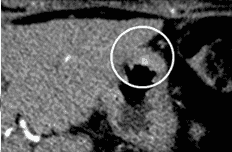

Рисунок 1. Множественные нейроэндокринные опухоли поджелудочной железы. Определяются только на фоне внутривенного введения контрастного препарата.

Рисунок 2. Нейроэндокринная опухоль желудка. Определяется только на фоне внутривенного введения контрастного препарата.

Рисунок 3. Нейроэндокринная опухоль кишечника. Определяется только на фоне внутривенного введения контрастного препарата.